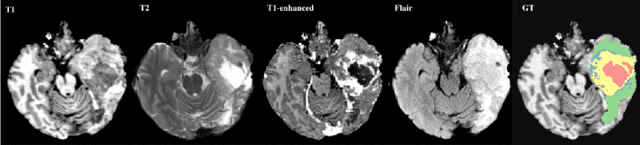

Abstract:Most research on novel techniques for 3D Medical Image Segmentation (MIS) is currently done using Deep Learning with GPU accelerators. The principal challenge of such technique is that a single input can easily cope computing resources, and require prohibitive amounts of time to be processed. Distribution of deep learning and scalability over computing devices is an actual need for progressing on such research field. Conventional distribution of neural networks consist in data parallelism, where data is scattered over resources (e.g., GPUs) to parallelize the training of the model. However, experiment parallelism is also an option, where different training processes are parallelized across resources. While the first option is much more common on 3D image segmentation, the second provides a pipeline design with less dependence among parallelized processes, allowing overhead reduction and more potential scalability. In this work we present a design for distributed deep learning training pipelines, focusing on multi-node and multi-GPU environments, where the two different distribution approaches are deployed and benchmarked. We take as proof of concept the 3D U-Net architecture, using the MSD Brain Tumor Segmentation dataset, a state-of-art problem in medical image segmentation with high computing and space requirements. Using the BSC MareNostrum supercomputer as benchmarking environment, we use TensorFlow and Ray as neural network training and experiment distribution platforms. We evaluate the experiment speed-up, showing the potential for scaling out on GPUs and nodes. Also comparing the different parallelism techniques, showing how experiment distribution leverages better such resources through scaling. Finally, we provide the implementation of the design open to the community, and the non-trivial steps and methodology for adapting and deploying a MIS case as the here presented.